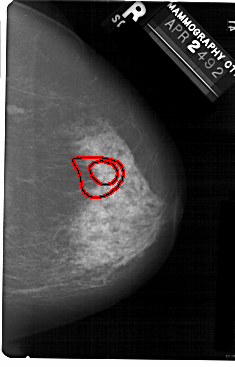

RIGHT_MLO LINES 5491 PIXELS_PER_LINE 3736 BITS_PER_PIXEL 12 RESOLUTION 43.5 OVERLAY

FILE: A_1127_1.RIGHT_MLO.OVERLAY

TOTAL_ABNORMALITIES 1

ABNORMALITY 1

LESION_TYPE MASS SHAPE ARCHITECTURAL_DISTORTION MARGINS SPICULATED

ASSESSMENT 5

SUBTLETY 1

PATHOLOGY MALIGNANT

TOTAL_OUTLINES 1

BOUNDARY